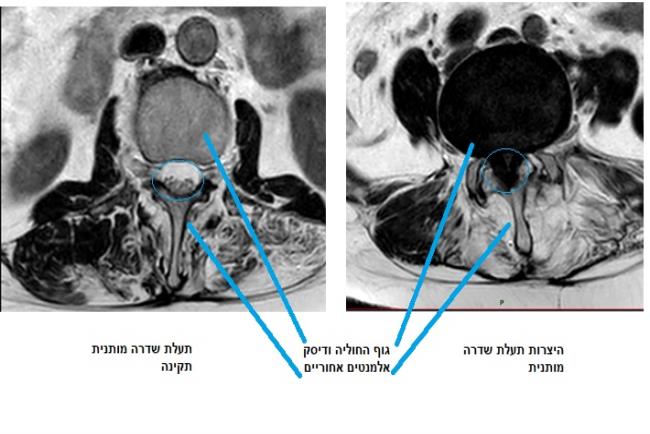

כאמור, היצרות תעלת השדרה נגרמת עקב פתולוגיות דומות. כתוצאה מהן קוטר התעלה קטן ואינו מספק את צורכי חוט השדרה הנמצא בתוכה. ההיצרות יכולה להיות מולדת או להתפתח בשל פתולוגיות מסוימות. הסיבה השכיחה ביותר להתפתחותה היא ניוונית(דגנרטיבית). תעלת השדרה שלנו מורכבת מגופי החוליות והדיסקים בחלקה הקדמי ובחלקים הצדדיים והאחוריים קשתות גרמיות, מפרקים וליגמנטים (רצועות). היצרות תעלה ניוונית נגרמת מהיפרתרופיה (גדילה לא תואמת) של כל אחד מהאלמנטים שתוארו לעיל.אילו תסמינים יעלו חשד להיצרות של עמוד השדרה?

האבחנה מתבססת על חשד העולה מתלונות המטופל, ולרוב הבדיקה גופנית תהיה תקינה (מאחר והמטפל נמצא במנוחה). כאמור, היצרות בתעלת השדרה המותנית לוחצת על זנב הסוס המורכב מעצבים ולא מחוט השדרה ועל כן, התלונות והנזק העשוי להיגרם מוגבל , נדיר שהיצרות תעלת שדרה מותנית תגרום לחסרים נוירולוגיים משמעותיים או מצב של אי שליטה בסוגרים. לשם אבחון סופי תתבצע גם בדיקת הדמיה, כאשר בדיקת הבחירה תהא לרוב בדיקת MRI בה ניתן לראות את כל הרקמות האזוריות (מבנים גרמיים רצועות, דיסקים ועצבים).